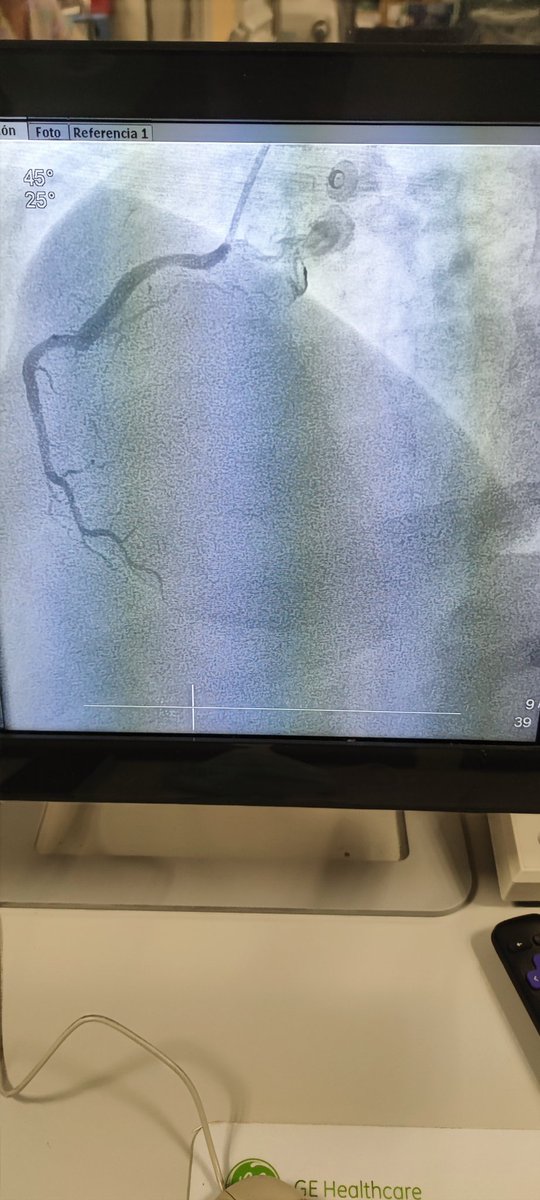

🫀⚡🧔🏻 45a, 🚬intenso, sedentario, obeso, HTA, #SICA #RadialFirst angio CD OTC agudizada TM disección ostial, Fullmetal CD 👌🏼 #MasterTheComplex #PCI #IVUS #Terumo #Azahi #BostonScientific #Medtronic